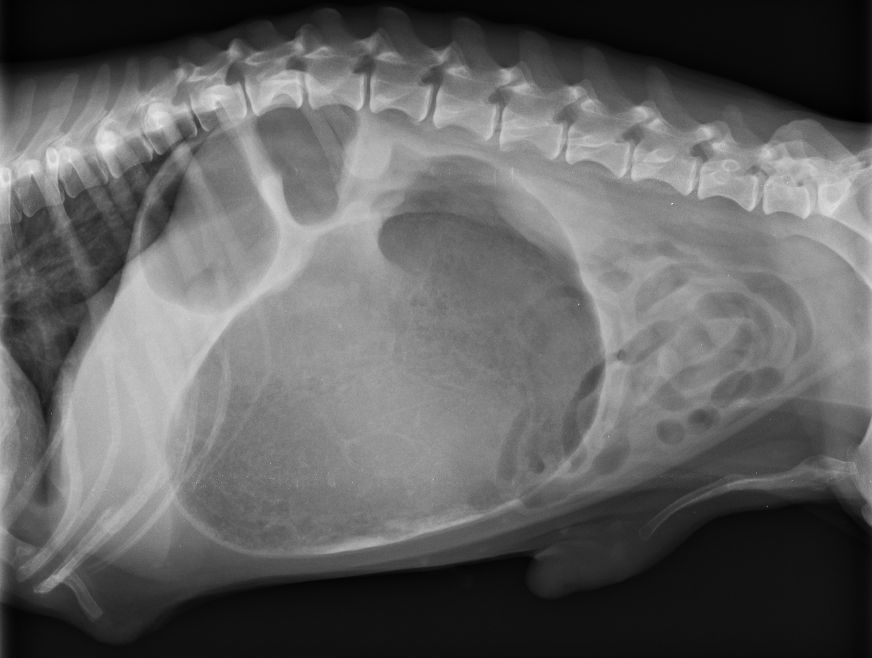

• 心包囊積液

心包囊積液